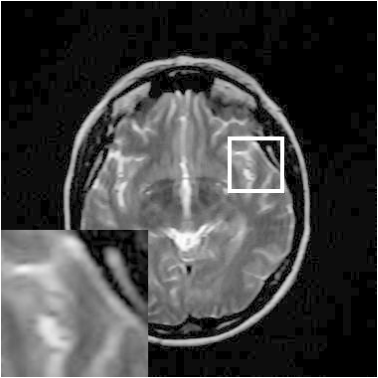

Figure 9: Reconstruction results for 30% radial sampling. (a) Original. (b)-(h) Reconstructed images. (i)-(n) The errors of six CSMRI methods.

As shown in Figs. 7, 8 and 9, Sparse MRI and DLMRI have a lot of unpleasant artifacts, Residual learning and U-net can eliminate most of artifacts, but are not ideal for restoring image details. However, the proposed method can reconstruct better MR images, which outperforms other competitive methods in visualization of structures reconstruction and artifacts removal. Meanwhile, we can see from the absolute error residuals for three sampling experiments that the proposed MDN algorithm restores a finer detail structure than other algorithms. Moreover, we present the PSNR and SSIM values in Table I for different algorithms, sampling masks and sampling rates. It is demonstrated that the proposed method provides better reconstruction performance and visual results than other competitive methods. We can also see the obvious improvement of all algorithms over zero-filling both in visualization. In particular, a higher SSIM value of Sparse MRI appears when using 30% variable density random sampling, however, Sparse MRI generates more artifacts than the proposed MDN.